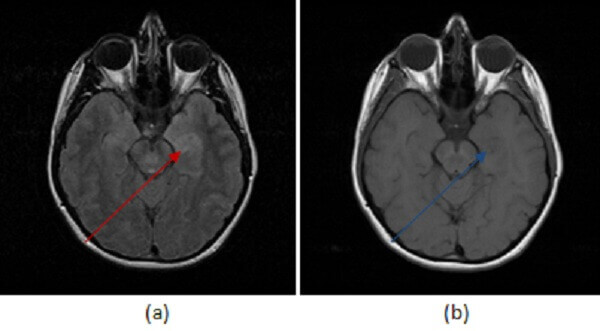

Figure 1: Increased (a,red arrow) FLAIR signal abnormality preferential for the left mesial temporal lobe is T1 hypointense (b, blue arrow ). It does not demonstrate restricted diffusion (c, green arrow) or enhance (not shown).

Understanding the imaging features of HSV encephalitis is important, since empiric antiviral therapy should be initiated if there is any suspicion for the condition. MRI is the most sensitive imaging modality. Imaging findings include T2/FLAIR signal abnormality involving the cortical and subcortical regions within the limbic system, especially the mesial temporal lobe. The findings are possibly bilateral but commonly asymmetric. There may be associated restricted diffusion on DWI and hemorrhage suggested by foci of decreased signal intensity on GRE sequences. Patchy or gyriform enhancement may be seen in these regions after contrast administration, or there may be no enhancement at all. The differential diagnosis also includes infarct and astrocytoma. A signal abnormality that lacks territorial restricted diffusion or that crosses vascular territories in a patient with sudden onset of symptoms and a suggestive LP help to differentiate HSV from infarct and tumor.